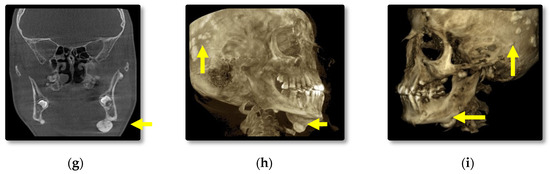

3.1. Radiographic Assessment

4.2. Osteomas

- Cankaya, A.B.; Erdem, M.A.; Isler, S.C.; Cifter, M.; Olgac, V.; Kasapoglu, C.; Oral, C.K. Oral and maxillofacial considerations in Gardner’s syndrome. Int. J. Med. Sci. 2012, 9, 137. [Google Scholar] [CrossRef] [PubMed]

- Almeida, F.T.; Pachêco-Pereira, C.; Porporatti, A.L.; Flores-Mir, C.; Leite, A.F.; De Luca Canto, G.; Guerra, E.N.S. Oral manifestations in patients with familial adenomatous polyposis: A systematic review and meta-analysis. J. Gastroenterol. Hepatol. 2016, 31, 527–540. [Google Scholar] [CrossRef] [PubMed]

- Wijn, M.A.; Keller, J.J.; Giardiello, F.M.; Brand, H.S. Oral and maxillofacial manifestations of familial adenomatous polyposis. Oral Dis. 2007, 13, 360–365. [Google Scholar] [CrossRef] [PubMed]